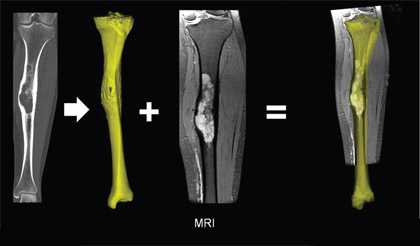

Очаговое изменение в диплоическом веществе свода черепа (рис.1215) и очаг в толще губчатого вещества тела позвоночника (рис.1216), состоящее из кавернозных полостей.

Морфологически различают первичную внутрикостную гемангиому и гемангиомы мягких тканей, вторично поражающих кости черепа (гемангиоматоз). Первичные внутрикостные гемангиомы растут медленно, как правило, расположены в губчатой кости. В большинстве они доброкачественные, но редко могут быть локально агрессивными. На КТ определяется рассасывание губчатого вещества с наличием радиальных костных балок. Гемангиома медленно растет (5-6лет), иногда самопроизвольно прекращает рост, сопровождаясь жировой инволюцией.

Гемангиома в плоских костях черепа - не частое образование, которое располагается преимущественно в диплоическом слое. Имеется разряженное строение губчатого вещества и толстые костные трабекулы, радиально расходящиеся в стороны. Очаг разряжения губчатого вещества в толще диплоического слоя определяется как зона↓плотности на КТ (стрелка на рис.1221) и↑МР-сигнала на Т2 и Flair (головки стрелок на рис.1219-1221).